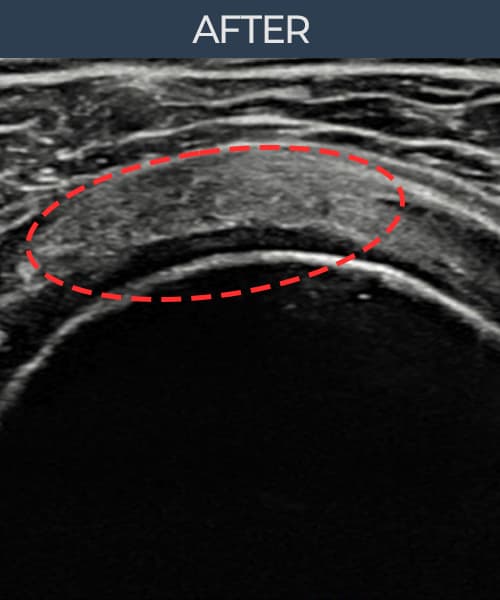

실제 환자의 시술 전후 초음파 영상입니다.

수술 없이 이뤄낸 회복을 직접 확인하세요.

모든 초음파 영상은 실제 환자의 동의를 받아 게시하였습니다. 개인차가 있으며 동일한 결과를 보장하지 않습니다.

[촬영시기:22.08.10]

[석회분쇄흡입술] 우측 어깨 극심한 야간 통증으로 수면이 불가능해진 50대 여성 환자로, X-ray에서 우측 극상근건 내 석회 침착이 확인되어 석회분쇄흡입술을 시행하였습니다.